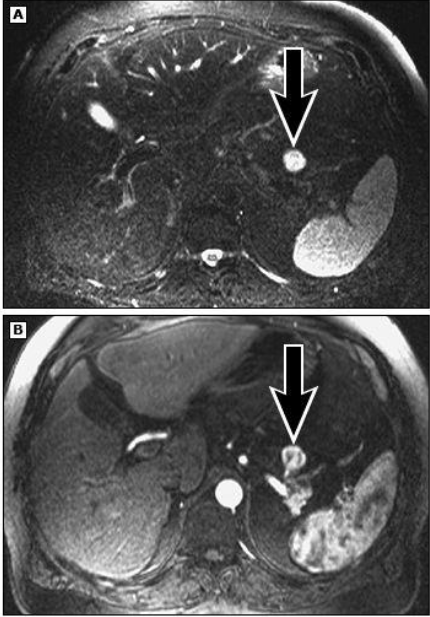

מהו הממצא

A

פסואודוציסטה בלבלב- דם,אפיתל ושאריות של חלבון שהצטבר

How well did you know this?

8

Q

IPMN

הרחבה של צינור הלבלב יחד עם ציסטה, מדובר בציסטה גידולית